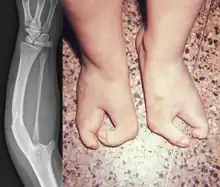

Van Den Berghe Dequeker syndrome, also known as ulnar hypoplasia-split foot syndrome is a very rare congenital limb malformation syndrome which is characterized by severe ulnar hypoplasia, absence of the index to pinky finger in both hands, and split-foot.[3]

It was first discovered in 1978 by H van de Berghe et al., when they described four males (consisting of three brothers and one maternal nephew) of a two-generation family with a "lobster-claw foot" and an "ulnar defect".[3] The lobster-claw architecture of the foot is described as the I and V toes being the only ones developed, resulting in the appearance of a split-foot. Morphology of the ulnar defect ranged from a shortened ulna to complete absence of the ulna with a curved, thickened radius. Van de Berghe et al. also noticed that some female members (the mother and maternal aunt of an affected male) showed minor hypoplasia and slight deformations of the toes, as well as shorter ulnas and marginally curved radii. At the time of discovery, ulnar aplasia occurred sporadically and infrequently, therefore, the documentation of this occurring familially was considered to be rare.[3]

The symptoms (split foot and ulnar hypoplasia) of the syndrome can be observed from birth.[1] During diagnosis, a doctor may try to rule out other possible diseases or refer the patient to a specialist.[1] Genetic counseling can be done for individuals with the syndrome who are planning on having children.[2] Treatment of the condition can include reconstructive surgery or the use of prosthetics to improve the ability to carry out daily tasks.[2]